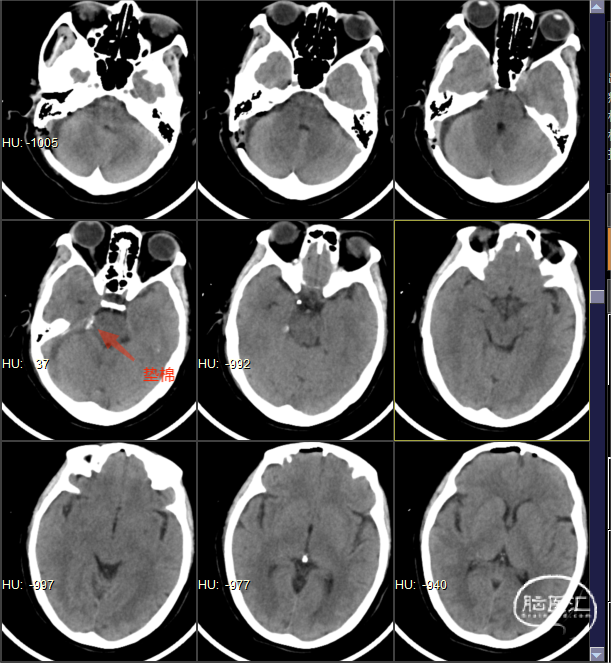

术后CT

患者术后右侧颜面部疼痛即缓解,无面部麻木,无面瘫,无听力下降。